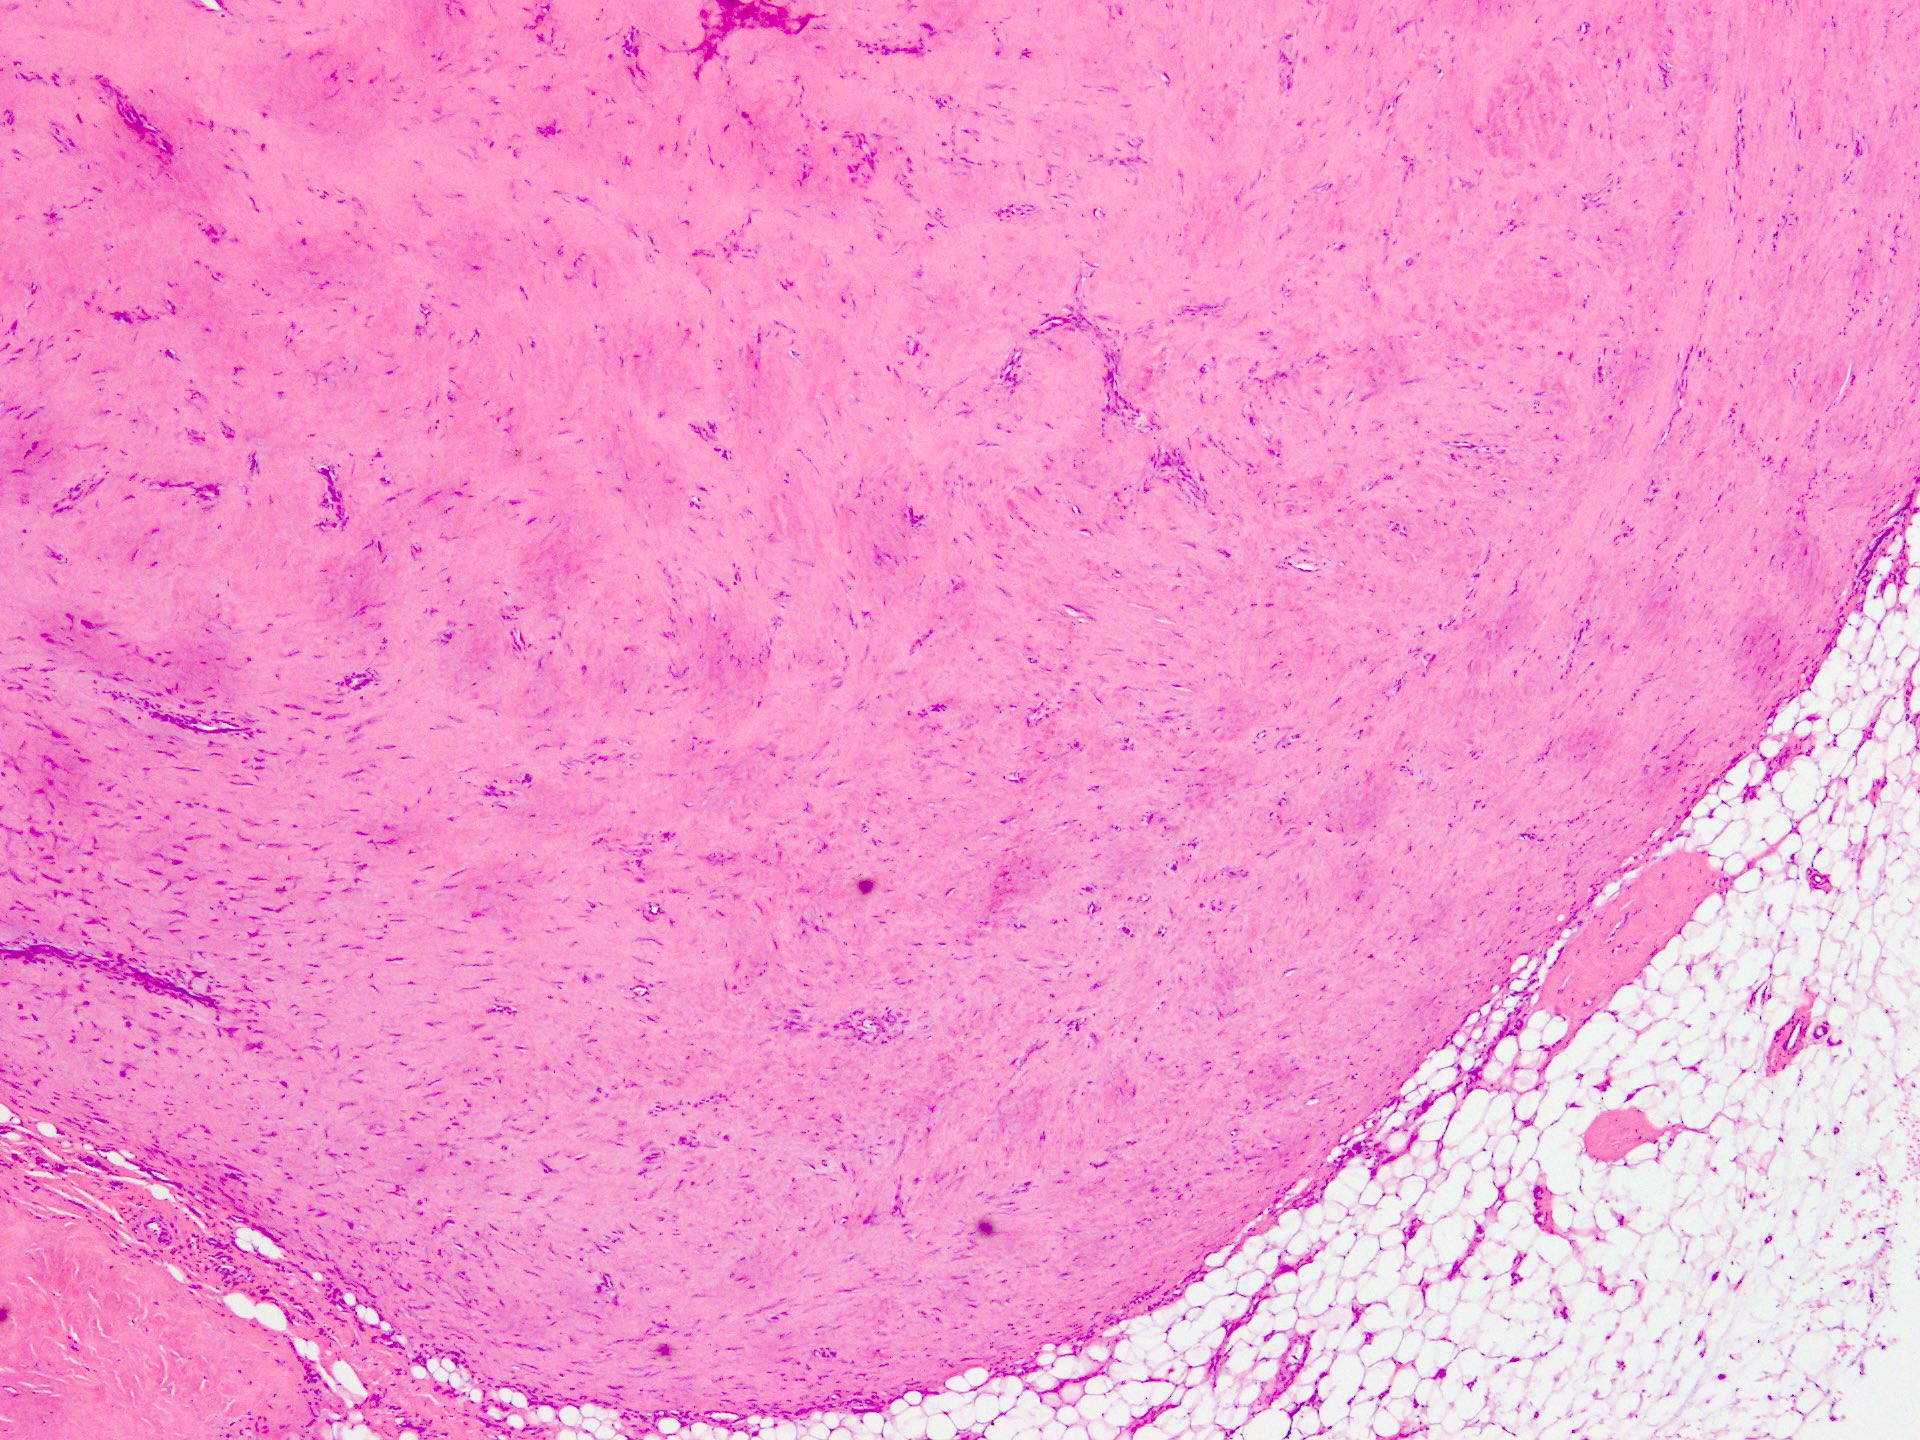

Microscopic (histologic) description

- Well circumscribed tumor of variable cellularity

- Cellularity mostly higher at tumor edges

- Bland spindle cells in a collagenous background

- Tumor has characteristic thin walled slit-like vessels

- Degenerative changes like myxoid / cystic change, osseous / chondroid metaplasia can be seen

- Bizarre pleomorphic cells can also be present

- Mitotically inactive

- Necrosis not present

- Cellular variant of fibroma of tendon sheath also exists; it overlaps morphologically with nodular fasciitis and fibrous histiocytoma (Cancer 1979;44:1945)

Microscopic (histologic) images

Contributed by Nasir Ud Din, M.B.B.S.

- Comment: Histology showed a well circumscribed, variably cellular lesion composed of bland spindle cells having regular nuclei arranged in sheets and fascicles. Thin walled vessels are present. The background is collagenous.

A 32 year old man has had painless swelling in the palm of his hand for 6 months. It was excised and the histology is shown in the above image. What is the most likely diagnosis?